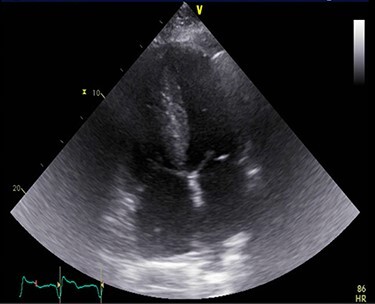

A 71-year-old male presented with DOE and syncopal episodes. His past medical history (PMH) was notable for hypothyroidism, hypertension (HTN), type II diabetes mellitus, obstructive sleep apnea (OSA), CTS, CHF, stage IV chronic kidney disease (CKD IV), complete heart block post-successful permanent pacemaker, paroxysmal atrial fibrillation (AFib). Labs were significant for mildly elevated troponin I (TnI) 0.12 ng/ml, elevated NT-proBNP 9655 pg/ml. EKG showed no acute ST-T changes. Transthoracic echocardiogram (TTE) was suggestive of infiltrative cardiomyopathy (Fig. 1).

Figure 1 .

A TTE showing homogenous speckled myocardium.